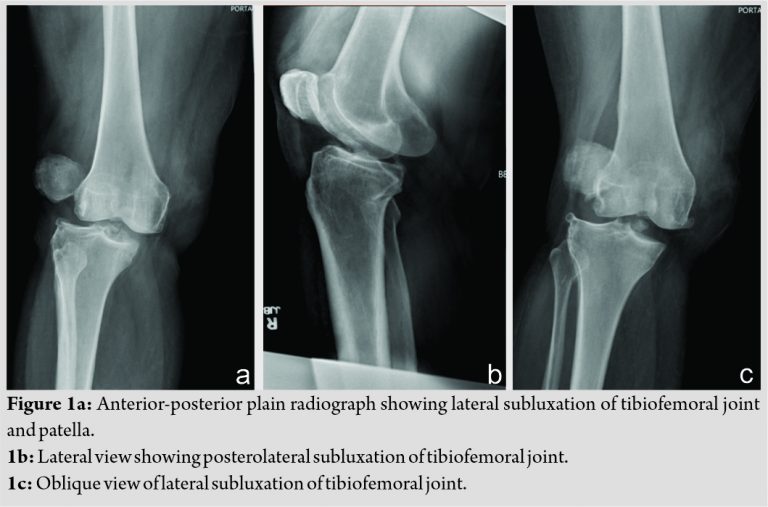

A 51-year-old morbidly obese female presented to the emergency department of our facility after sustaining a fall from standing height while at home. She described a rotatory mechanism and an inability to bear weight on her right lower limb due to pain and instability at the knee. On examination, the invagination of the skin was noted at the medial joint line of the knee in a characteristic dimple sign. Posterior tibial and dorsalis pedis pulses were palpable bilaterally at 2+ and 1+, respectively, with no signs of hypoperfusion to the right foot. All compartments were soft, and no pain with passive range of motion was noted at the ankle and foot. Sensory and motor innervation was intact. Ankle-brachial indices (ABIs) of bilateral lower extremities were documented at 1.10. Neurovascular status was closely monitored throughout the patient’s stay. Further, vascular studies, such as angiography, were deferred. Radiographs revealed lateral subluxation of the tibiofemoral joint with a wide medial compartment and lateral dislocation of the patella (Fig. 1a, 1 b, 1c).

The emergency room physician urgently sedated the patient and the orthopedic trauma team, which was inclusive of a junior and senior resident as well as the attending surgeon, performed several attempts at reduction. The reduction technique employed consisted of traction and counter-traction with a force directed to correct the deformity. A lateral-to-medial force failed to reduce the patella. After unsuccessful closed reduction, the patient was transported to the OR for closed versus open reduction under general anesthesia. She was placed supine on the table with a bump under the right hip and with her right leg slightly flexed on a foam pad. The leg was prepped in the usual sterile fashion and before the incision was made, the hip was flexed, and the knee was flexed to 120 with internal rotation of the limb. A large valgus force was applied at the distal thigh, as described by Tateda et al. [7]. The dislocation was reduced, and the dimple sign disappeared. The limb was brought out to extension and reduction was confirmed with fluoroscopy in the anterior-posterior and lateral views. Some lateral subluxation of the patella remained (Fig. 2a, 2b). It was felt that this maneuver allowed the medial femoral condyle to be pulled back through the buttonhole in the medial retinaculum.